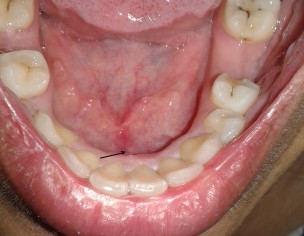

I don't remember how long its been there but at least its been a few months since I've been feeling a small hard immovable lump on the floor of mouth against jaw bone. Its hardly visible but can be felt with tongue and by pressing against it. It wasn't painful until recently when I started touching it more often it feels like ulcerated and is slightly painful sometimes only. Reading articles on google and viewing images is nerve-shattering. Does this need x-ray or biopsy? Can anyone suggest something.